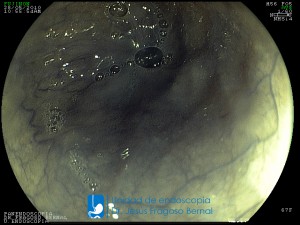

La Unidad de Endoscopía fue creada en 2002 por el Dr. Jesús Fragoso Bernal, es pionera en el estado por la utilización de la tecnología más avanzada, que nos permite ofrecer servicios integrales de diagnóstico y tratamiento para las enfermedades del aparato digestivo.